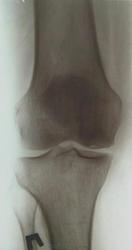

Здравствуйте! Давненько ничего не выкладывал. Нужна помощь. Женщина 1937 г.р. Жалобы на боли в правом коленном суставе уже давно. Долго ставили деф артроз.

Думаю что здесь частичный аваскулярный некроз медиального мыщелка бедренной кости. Ну а теперь вопросы:

Насколько понимаю - болезнь Кенига.

Да, но здесь часть эпифиза рассосалась, осталась только частично разрушенная субхондральная пластинка. Вот и думаю что это за стадия

Я так понимаю что Кенига (рассекающий остеохондрит) и аваскулярный некроз - это разные заболевания. По крайней мере на radiologyassistant так.